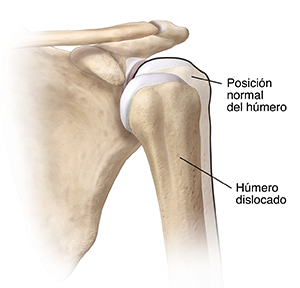

Si se dislocó el hombro, el hueso de la parte superior del brazo (húmero) se salió de la articulación del hombro. Es la articulación grande del cuerpo que se disloca con más frecuencia. La dislocación suele deberse a una fuerza importante que separa la bola de la articulación del hombro (la parte superior redondeada del hueso de la parte superior del brazo) de la cavidad de la articulación (glenoidea).

El hombro puede dislocarse parcial o totalmente. La dislocación parcial ocurre cuando la cabeza de la parte superior del brazo se sale de forma parcial de la cavidad del hombro. La dislocación total ocurre cuando la cabeza de la parte superior del brazo se sale por completo de la cavidad del hombro.